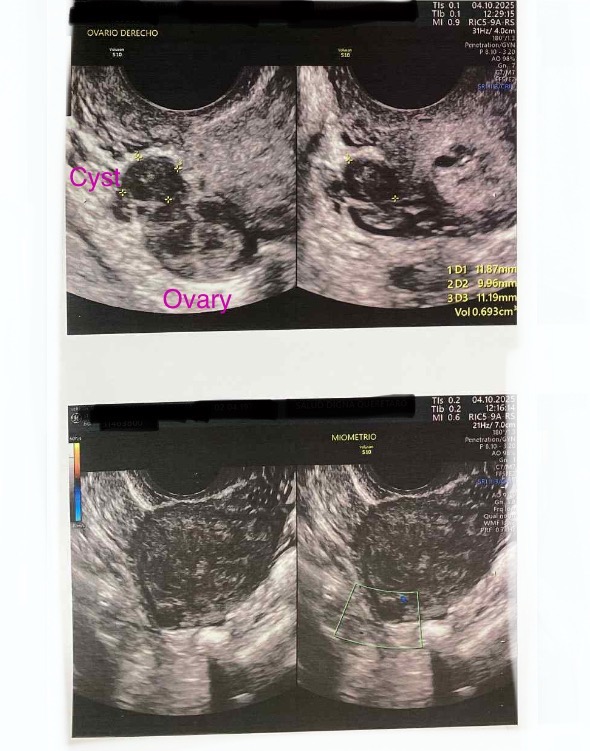

For context, endometriosis is a chronic inflammatory disease where tissue similar to the uterine lining grows outside the uterus, causing lesions, cysts, adhesions, and nerve involvement. In my case, the disease is affecting my ovaries, pelvic cavity, ligaments, and possibly the intestines, and adenomyosis is causing additional pain, inflammation, and heavy bleeding inside the uterine muscle.

- Excision of ovarian endometriomas (cysts)

Para quienes no estén familiarizados, la endometriosis es una enfermedad inflamatoria crónica en la cual tejido similar al endometrio crece fuera del útero, formando lesiones, quistes, adherencias y afectando nervios y órganos. En mi caso, la enfermedad está afectando mis ovarios, la cavidad pélvica, ligamentos, y posiblemente el intestino. La adenomiosis está causando dolor adicional, inflamación y sangrado abundante dentro del músculo uterino.

- Excisión de endometriomas ováricos (quistes)